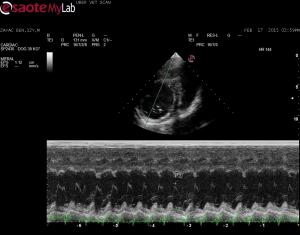

– echo did show a dilated LV and poor systolic function, decreased FS%, elevated EPSS so I am concerend about occult DCM

Of course the clip you want, I did not save! I have added two tranverse right parasternal views, if this may help? They are slightly obliqued ๐